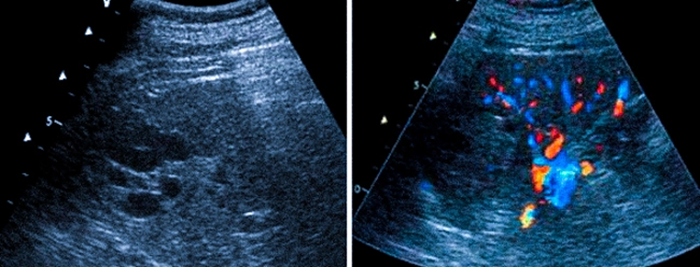

УЗДГ селезенки — представляет собой неинвазивный, информативный и безопасный метод диагностики. Обследование применяется для оценки сосудов, по которым кровь поступает по селезеночной артерии от брюшной аорты. Приток крови происходит по селезоночной вене, по пульпарным и трабекулярным венам.

Ультразвуковая допплеография селезенки выявляет аневризмы и окклюзии, артериовенозную фистулу, а также другие патологические изменения. Обследование определяет форму и размеры органа, новообразования и гематомы, состояние лимфоузлов.